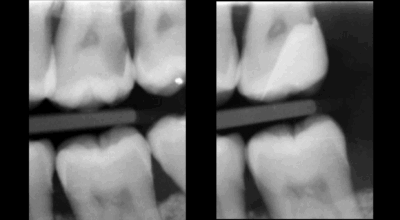

Cas clinique

Traitement canalaire : 80-95% de taux de succès